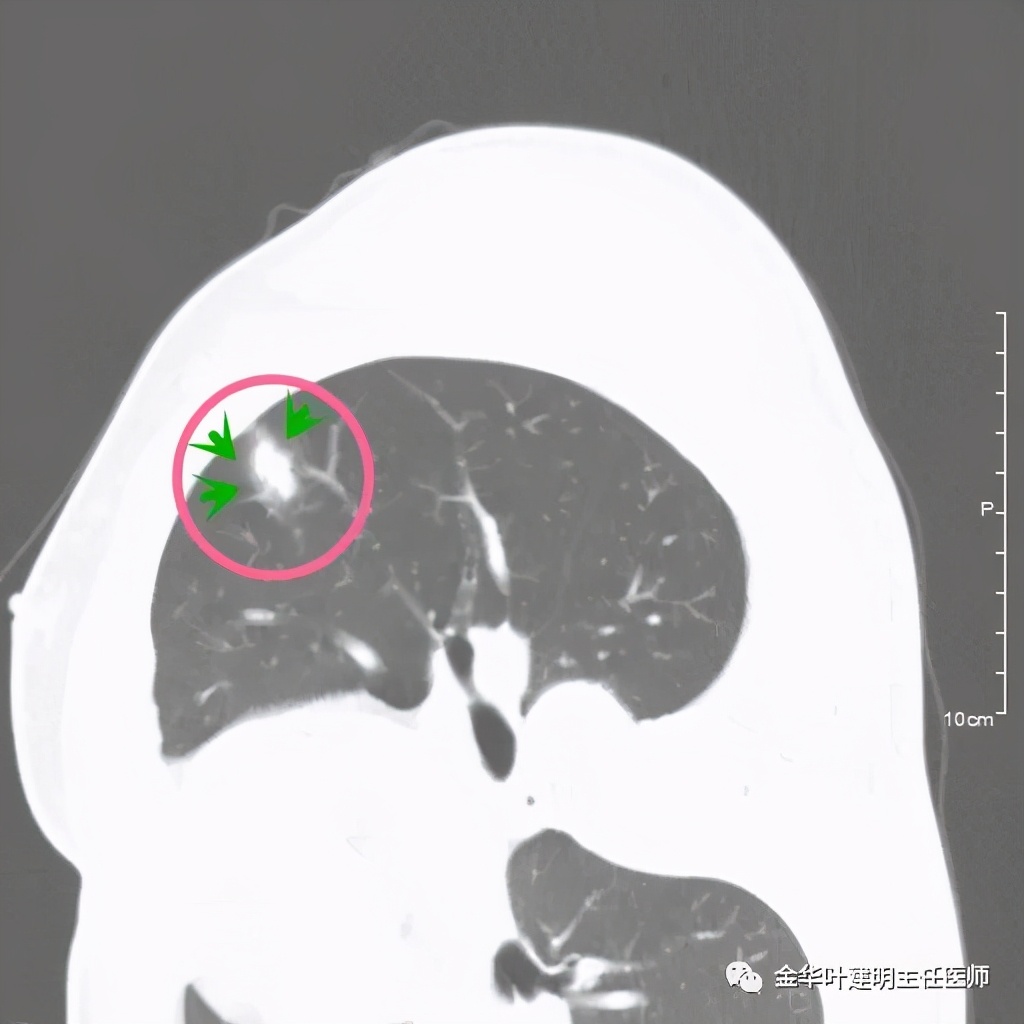

上图示有血管征,与病灶关系较密切

上图示血管与病灶临近,但没有被病灶牵拉从而进入病灶

上图血管有分支进入病灶

我们见左上实性病灶,主病灶旁有卫星灶,有血管进入,但也有贴边走行,边缘略显模糊,膨胀感与细毛刺不明显,收缩力也不明显。下面是其靶扫描的片子:

病灶实性,但收缩力弱,绿色箭头示病灶边缘有一圈晕征(模糊且均匀)

病灶实性,但收缩力弱,没有细毛刺征,实性部分比较圆润,绿色箭头示病灶边缘有一圈晕征(模糊且均匀)